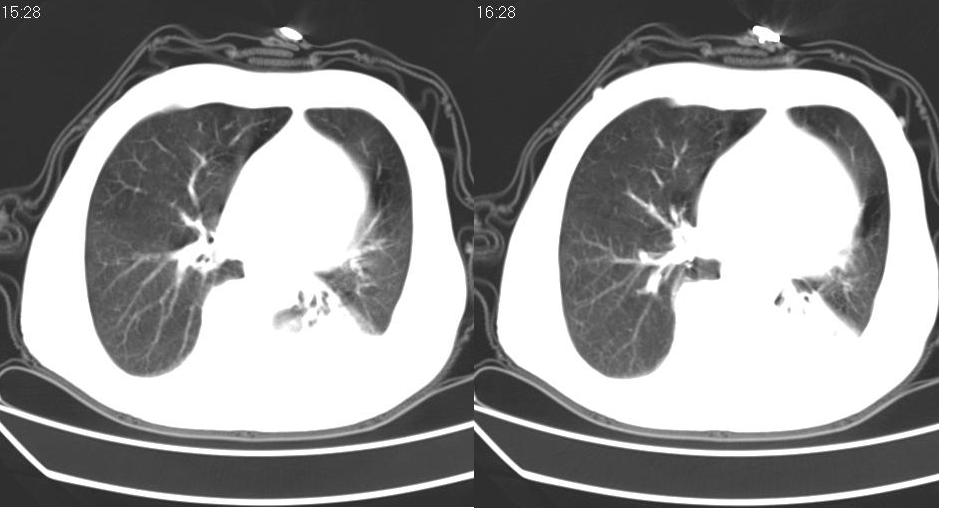

左下肺体积缩小,密度增高,见片增密影。边界模糊,见支气管充气像,肺门纵隔无异示,心脏气管左移,左侧胸腔少量积液。考虑肺部感染伴部分肺不张[有脑梗塞病史坠积性肺炎可能]

1、左肺下叶后基底段炎症并膨胀不全。

2、左侧胸腔积液。

左下肺体积缩小,密度增高,并见大片状致密影,边界模糊,其内见支气管充气像,肺门纵隔无异常,心脏气管左移,左侧胸腔少量积液。考虑:左肺炎性病变伴不张。

3.两肺慢支改变。